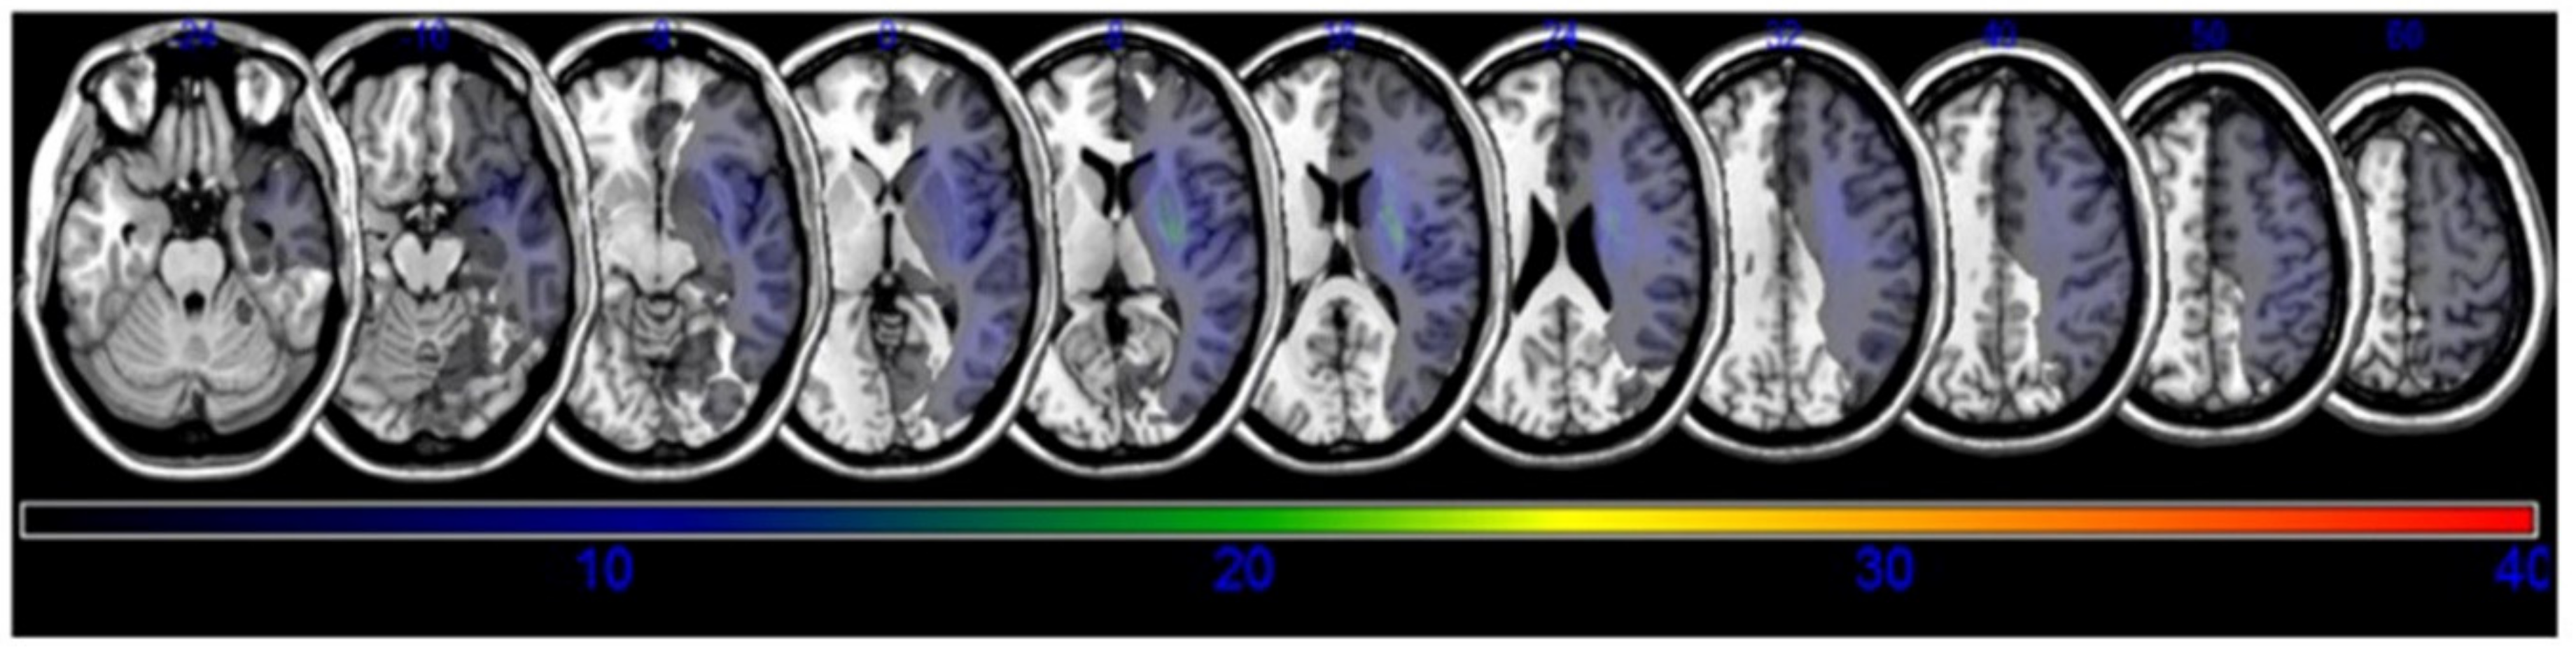

3.2. Lesion Analysis

| MNI Coordinates (X, Y, Z) | BM Z max | n Voxels | Anatomical Brain Lesion |

|---|---|---|---|

| 34, −38, 35 | 2.90267 | 114 | Parietal lobe, Sub-Gyral |

| 29, −26, 32 | 3.38958 | 111 | Frontal lobe, Superior longitudinal |

| 29, 13, 28 | 2.85527 | 116 | Frontal lobe, Sub-Gyral |

| 29, −27, 30 | 3.17468 | 114 | Posterior corona radiata |

| 38, −35, 15 | 2.65207 | 106 | Temporal lobe, STG |

| 42, −41, −7 | 2.55235 | 115 | Temporal lobe, MTG |